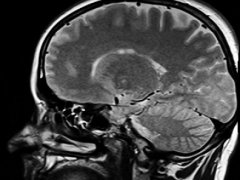

脊髓肿瘤 是脊髓中大量的异常细胞,它们的生长已经失去控制。脊髓肿瘤分为4级,等级越低,生长越慢。1级和2级肿瘤的生长速度比3级和4级慢。那么,脊髓肿瘤一级复发了怎么办?...

问: 什么是脊髓肿瘤 ?MRI核磁影像如何解读瘤种? 答:脊髓肿瘤是位于椎管(神经通道)中的神经和神经周组织肿瘤。根据肿瘤与脊髓和硬脑膜(包裹神经的膜)之间的位置关系...

Q:脊髓肿瘤是良性还是恶性? A:脊髓肿瘤指发生于脊髓本身、以及椎管内与脊髓邻近的肿瘤。 按肿瘤与脊髓关系,由内向外可以分为三类:脊髓髓内肿瘤,脊髓髓外硬脊膜下肿瘤,硬...